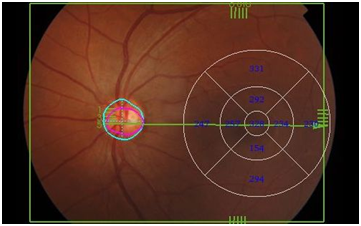

All the subjects underwent a comprehensive ophthalmic examination on slit lamp biomicroscope by an Ophthalmologist. To visualize full choroidal thickness Swept Source OCT (Topcon Triton) was employed. SS OCT performs scanning with the speed of 50,000 scans per second with the beam of wavelength 1050nm. The choroid thickness is defined as the thickness from Bruch’s membrane to the inner scleral border. Radial scans were taken and 3-Dchoroidal thickness maps were obtained. Choroidal thickness in 9 different zones were obtained namely; subfoveal central zone, nasal, temporal, superior and inferior of paracentral zones; and nasal, temporal, superior and inferior of peripheral zones (Figure 1). All the scans were performed by a trained ophthalmic technologist and analyzed by an experienced ophthalmologist.

Figure 1 Grid: 9 different zones namely; subfoveal central zone, nasal, temporal, superior and inferior of paracentral zones; and nasal, temporal, superior and inferior of peripheral zones.